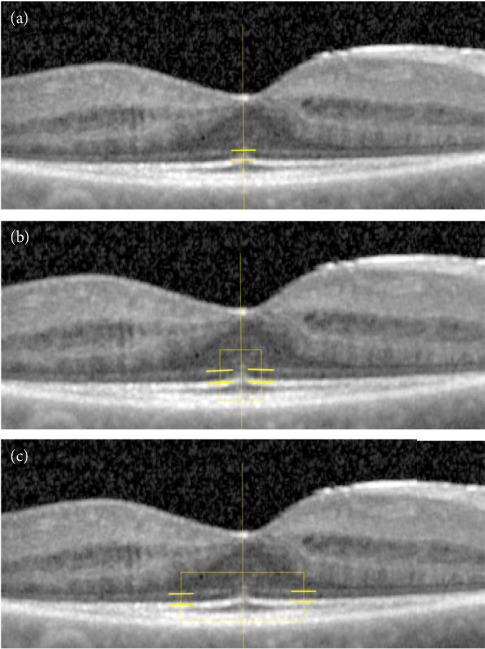

Purpose: With degeneration of the photoreceptors in retinitis pigmentosa (RP), the reflectivity of the ellipsoid zone (EZ) decreases. We aimed to study characteristics of the EZ and its reflectivity in a cohort of patients with PRPF31-associated autosomal-dominant RP (PRPF31-adRP) and a possible relationship to EZ width and best-corrected visual acuity (BCVA). Methods: EZ width and relative EZ reflectivity (rEZR) were assessed in 32 patients with PRPF31-adRP. EZ width was measured on a horizontal SD-OCT scan through the fovea of the right eye. On the same OCT scans, rEZR was measured at the foveola, temporal and nasal parafoveola and fovea. Results: Total EZ width revealed a significant negative correlation with age (r s  = -0.418, p=0.017). Foveolar rEZR revealed a significant negative correlation with age (r s  = -0.403, p=0.022), but was not significantly correlated with BCVA (foveolar: r s  = -0.151, p=0.410), in contrast to parafoveolar rEZR (r s  = -0.365, p=0.0399), which was significantly correlated with BCVA. The ratio of foveal and parafoveolar rEZR correlated significantly with total EZ width (r s  = 0.358, p=0.044). Conclusions: The EZ reflectivity (EZR) can be measured reliably using freely available software. The correlation we observed between rEZR and BCVA leads us to the conclusion that rEZR may be an additional marker in observational and therapeutic trials.

Abstract Image